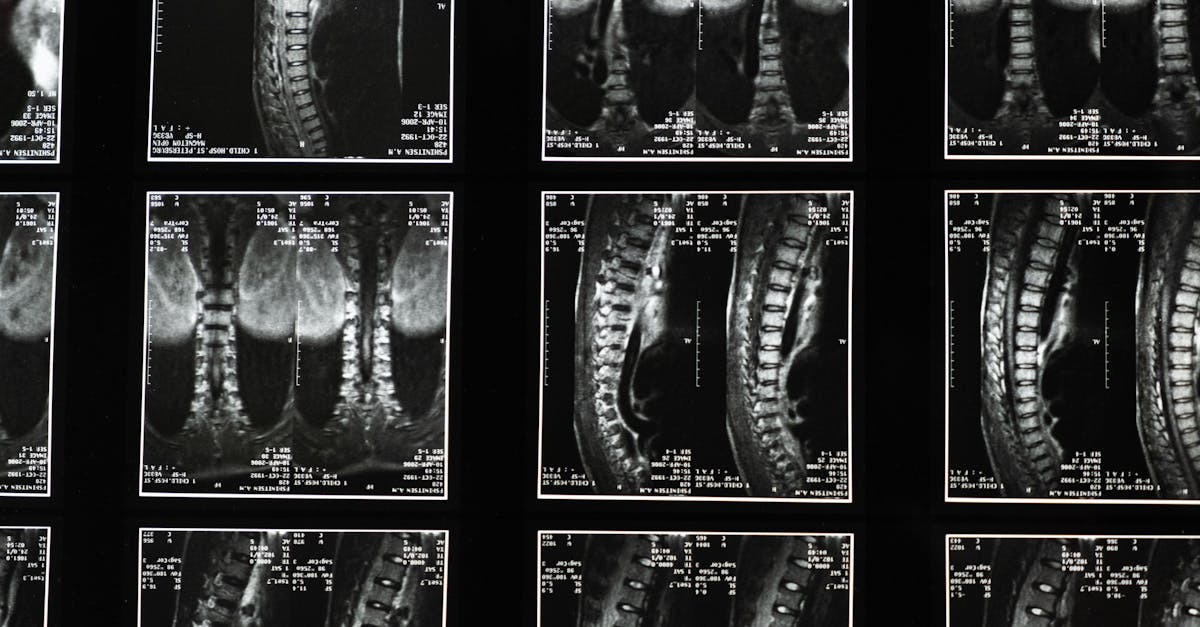

Le processus de décompression commence par l’installation du patient sur une table spécialement conçue, comme la table SpineMed. Ce dispositif permet d’appliquer une traction douce qui crée un espace entre les vertèbres. En augmentant cet espace, la décompression atténue la pression qui pèse sur les nerfs spinal, contribuant ainsi à une réduction efficace de la douleur. La circulation sanguine s’en trouve également améliorée, ce qui favorise la régénération des tissus endommagés et peut accélérer le processus de guérison.

La sténose spinale, caractérisée par un rétrécissement du canal rachidien, peut entraîner des douleurs handicapantes au dos et aux jambes. La décompression neurovertébrale, grâce à des machines comme la table SpineMed, crée un espace entre les vertèbres, réduisant ainsi la compression sur les zones touchées. Ce mécanisme permet non seulement un soulagement immédiat de la douleur, mais contribue également à une meilleure régénération des tissus endommagés.